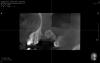

red_butler Опубликовано 31 января, 2013 Поделиться Опубликовано 31 января, 2013 Пришла пациентка через 7 месяцев после синуслифта, посмотрел кт и ... в общем давайте обсудим. Сама операция без видимых проблем, послеоперационный период гладкий. Делал даском, в пазухе байосЧто ДЕЛАТЬ Ссылка на комментарий

Bier Опубликовано 31 января, 2013 Поделиться Опубликовано 31 января, 2013 я так понимаю, что автора волнует отек слизистой, чуть ли не на всю пазуху. 2 Ссылка на комментарий

art.podzhigant Опубликовано 31 января, 2013 Поделиться Опубликовано 31 января, 2013 кт до принципиально надо глянуть....отек слизистой гайморовой пазухи трудно не заметить Ссылка на комментарий

777white Опубликовано 31 января, 2013 Поделиться Опубликовано 31 января, 2013 Может и до операции был синусит? ЛОР консультация? Посмотреть бы еще что с биоосом стало... Может была перфа и там каша а не кость... Хотя по кт вроде неплохо... Ссылка на комментарий

777white Опубликовано 31 января, 2013 Поделиться Опубликовано 31 января, 2013 На 1ом снимке что такое от основного "комка" справа? Ссылка на комментарий

red_butler Опубликовано 1 февраля, 2013 Автор Поделиться Опубликовано 1 февраля, 2013 Выкладываю кт до. В первую очередь интересует состояние слизистой, и как туды винты теперь ставить. И конечно вопрос ПОЧЕМУ, хотя причинно-следственная связь вполне очевидна. Забыл написать - синус был двух-сторонний и слева все o`k Ссылка на комментарий

777white Опубликовано 12 февраля, 2013 Поделиться Опубликовано 12 февраля, 2013 Выкладываю кт до. В первую очередь интересует состояние слизистой, и как туды винты теперь ставить. И конечно вопрос ПОЧЕМУ, хотя причинно-следственная связь вполне очевидна. Забыл написать - синус был двух-сторонний и слева все o`kПо к/т уже до операции слизистая утолщена была, то есть воспалена. ИмхоЯ за то что там инфицированный графт как каша, кости там нет... Чистить надоЖдем Лора Ссылка на комментарий

kriokov Опубликовано 12 февраля, 2013 Поделиться Опубликовано 12 февраля, 2013 (изменено) про затеки не совсем понял. То что отслаивать пошире и поглубже согласен, а так графта получилось не густо, не во всей " бухте" графт. И неполная септа там похоже до. Изменено 12 февраля, 2013 пользователем kriokov Ссылка на комментарий

red_butler Опубликовано 26 февраля, 2013 Автор Поделиться Опубликовано 26 февраля, 2013 Продолжаю, лор посмотрел - реактивные явления, противопоказаний к имплантации нет. На всякий случай сделал новое КТ, завтра второй этап. Ревизия и винты с синусом. Вот к чему приводит жадность с биоосом Ссылка на комментарий

DShu Опубликовано 26 февраля, 2013 Поделиться Опубликовано 26 февраля, 2013 Продолжаю, лор посмотрел - реактивные явления, противопоказаний к имплантации нет. На всякий случай сделал новое КТ, завтра второй этап. Ревизия и винты с синусом. Вот к чему приводит жадность с биоосом Ну что, выглядит намного лучше. Теперь главное не промахнуться и попасть точно в комок)) 1 Ссылка на комментарий